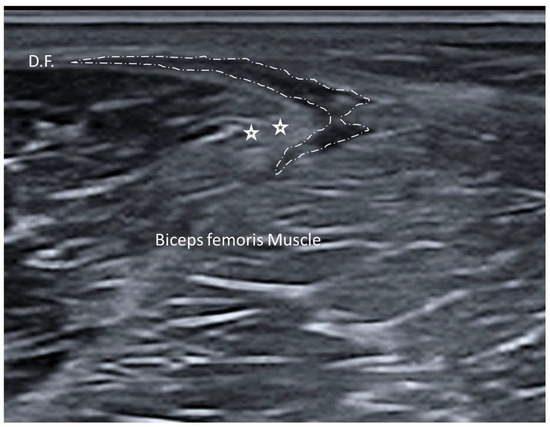

3.1. Normal Ultrasonographic Appearance of Fasciae

- Wilke, J.; Schwiete, C.; Behringer, M. Effects of Maximal Eccentric Exercise on Deep Fascia Stiffness of the Knee Flexors: A Pilot Study using Shear-Wave Elastography. J. Sports Sci. Med. 2022, 21, 419–425. [Google Scholar] [CrossRef] [PubMed] [PubMed Central]